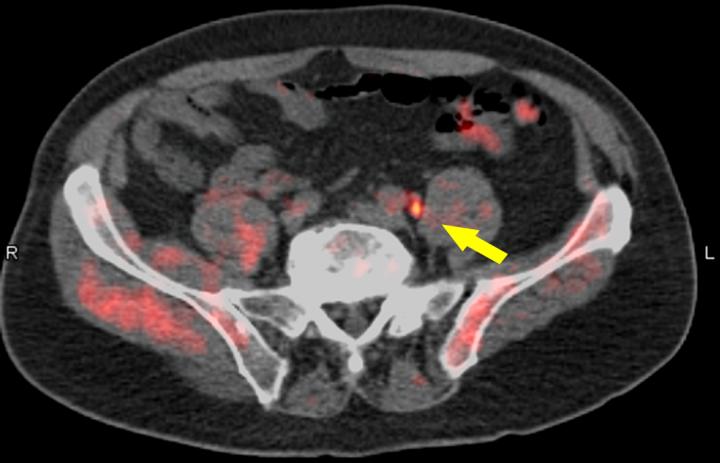

For the LOCATE trial (ID# NCT02680041), 213 men with biochemically recurrent prostate cancer were evaluated with 18F-fluciclovine PET/CT after having negative or equivocal findings on conventional imaging, such as a bone scan, CT or magnetic resonance imaging (MRI). This first prospective multicenter study was conducted at 15 sites in the U.S., including both private practices and academic settings. It focused on the association between scan positivity and the clinical variables of recurrence site, practice setting, prostate-specific antigen (PSA) level, and Gleason score (system of grading prostate cancer). Questionnaires completed by treating physicians documented changes in management after the PET study.

Trial results showed that 59 percent (126/213) of patients had their clinical management changed by findings from 18F-fluciclovine imaging. Of those changes, 78 percent (98/126) were classified as "major" (i.e., a change in treatment modality). Disease was detected in the prostate, as well as other tissue, including pelvic and abdominal lymph nodes and, less commonly, bone. Both positive and negative scans impacted patient management. No difference was seen in the rate of positive scans or in the rate of management changes between private practices and academic settings. In addition, no association was found between Gleason score at diagnosis and positive scans.